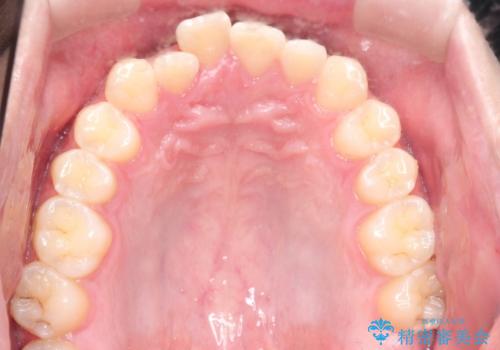

- 前歯の歯並びの改善を希望され来院された患者様です。

初診時の歯並びの状態としては、上下ともに前歯部の中等度以上のがたつき(叢生)があり、右の前歯が1本飛び出した状態でした。

抜歯は行わず上下顎ともに、主に歯列弓の拡大とディスキング(歯と歯の間に隙間を作る処置)を行い叢生を改善しました。